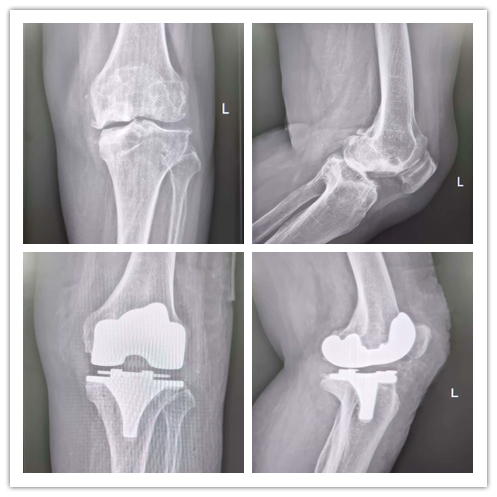

在公园里散步、与孙儿嬉戏、自由上下楼梯……这些看似平凡的日常,对许多深受膝关节疾病困扰的人来说却是一种奢望。当保守治疗无法缓解疼痛,当膝关节变形日益严重,人工膝关节置换手术便成为重启高质量生活的钥匙。 什么是膝关节置换? 膝关节置换手术,是一种将膝关节内受损的软骨及部分软骨下骨切除,并替换为人工设计的假体组件,是一种通过人工关节(采用金属、高分子聚乙烯、陶瓷等材料)置换受损膝关节,以恢复关节功能、减轻疼痛及改善患者的生活质量的治疗方法。 人工膝关节主要包括股骨髁、胫骨垫片、胫骨平台三部分。股骨髁和胫骨平台被固定在股骨和胫骨上,代替被除去的骨损伤部分,通常采用钴铬钼合金、钛合金等,具有极高的耐磨性、良好的生物相容性及机械强度。胫骨垫片附着于胫骨平台上,运动时股骨髁与垫片不断滚动摩擦,垫片承担半月板减少冲击和摩擦的作用。胫骨垫片材质为高分子聚乙烯,具有摩擦系数小、耐磨、抗压、抗氧化等特点。人工膝关节假体的使用寿命通常可以达到15-25年。 什么时候考虑膝关节置换手术? 膝关节是人体最大且最复杂的关节。膝关节的主要结构包括股骨下端、胫骨上端及髌骨关节面。当膝关节出现如晚期膝骨关节炎、类风湿关节炎等问题,引起关节软骨磨损、关节畸形,出现持续的关节疼痛、活动障碍等症状,通过药物、理疗等手段医治无效时,就可以考虑进行人工膝关节置换手术。 术后多久能恢复? 如无特殊情况,膝关节置换术后1-3天即可下床缓慢行走,术后应注意休息、避免剧烈运动,并在医生的指导下进行康复训练,包括膝关节屈伸活动度锻炼、下肢肌力锻炼、踝泵动作等。术后以及康复训练中出现疼痛属于正常现象,3-6月内可逐步恢复。 总而言之,新的膝关节替换原有严重损伤关节后,能够有效解决疼痛和行动不便等困扰。患者日常行动更便捷,提高了生活质量和体验,生活有了更多可能性。但仍需要遵医嘱,在进行康复训练时,务必确保动作轻柔、缓慢,避免过度用力或过度弯曲膝关节,以免引起不适或损伤。如果在训练过程中出现任何不适,应立即停止并咨询医生。 案 例 张女士,60岁,双膝关节疼痛3年余,经过药物治疗和玻璃酸钠关节腔注射后,疼痛症状仍反复,近1月左膝关节症状加重伴活动受限,右膝行走时也时有疼痛。为求系统治疗,前往桂平市中医医院门诊就诊,门诊以“双侧重膝关节骨性关节病”收入院。住院后钟军主治医师询问病史,结合影像学资料并详细查体:左膝关节肿胀、轻度內翻畸形,膝关节内外侧间隙压痛,过曲过伸疼痛,浮髌试验阴性,膝关节活动度0°-90°。 张女士入院后完善了相关检查,以排除手术禁忌症。随后,在骨一科蒋积满团队及手术麻醉室的密切配合下,为其顺利进行了左膝关节表面置换手术。术中,医护人员协同无间,操作精准熟练,在腰硬联合麻醉的辅助下,圆满完成了左膝关节表面置换术。手术过程顺利,手术出血少,术后安全返回病房。 经过手术及术后康复治疗,张女士已能独立行走,彻底摆脱了左膝关节疼痛和活动受限的困扰,生活质量得到显著提高。张女士表示:“没想到手术效果这么好,现在随便走,一点都不痛”!全膝关节置换术,这不仅是骨科技术实力和服务能力取得突破的重要体现,还为辖区患者解除了痛苦,让患者在家门口就能享受到优质的医疗服务,它让无数像张女生这样的患者解除了疾病带来的痛苦,重新拥抱生活的美好。桂平市中医医院骨科将继续致力于医疗技术的创新和发展,为更多患者提供精准、高质量的医疗服务! 健康咨询电话 0775—3395567 门诊地址 桂平市中医医院 急诊楼一楼 骨科门诊 住院部地址 桂平市中医医院 1号楼17楼骨一科 声明:本文仅作医疗知识科普,不作为诊疗方案推荐。具体治疗需经专业医生评估。 |